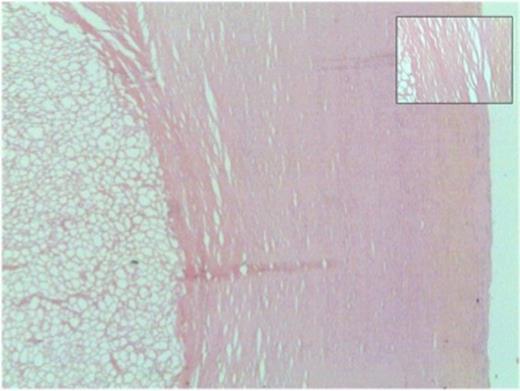

Microscopically, both nodules showed similar histological features. The larger nodule required prolonged, gentle decalcification before reasonable tissue sections could be obtained. Each had a thick shell of dense paucicellular collagen arranged as concentric layers with only a few fibroblasts and inflammatory cells present peripherally (Figures 4b and 5). The shell was devoid of cartilage and it encased necrotic adipose tissue (Figure 6) in which there was focal dystrophic calcification. No granulomatous inflammation, lung parenchyma, abscess formation, caseous type necrosis or neoplasm was identified.

Thick shell of paucicellular collagen surrounding necrotic fat (40x magnification). Inset: Closer view of concentrically arranged thin layers of collagen